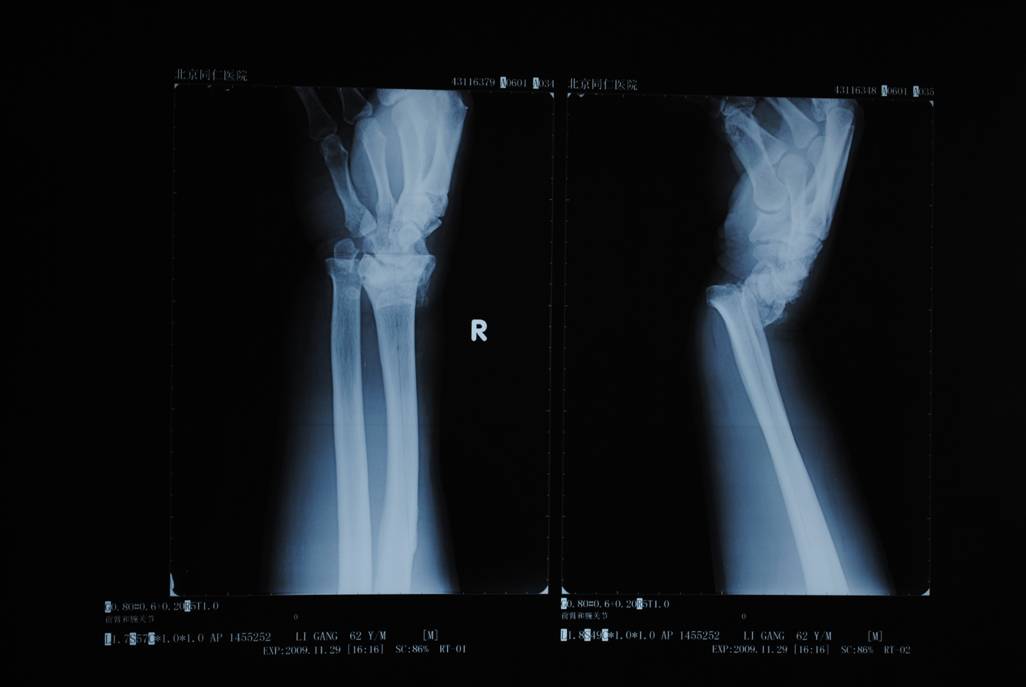

橈骨遠端骨折術前

橈骨遠端骨折術后

橈骨遠端骨折術前 橈骨遠端骨折術后